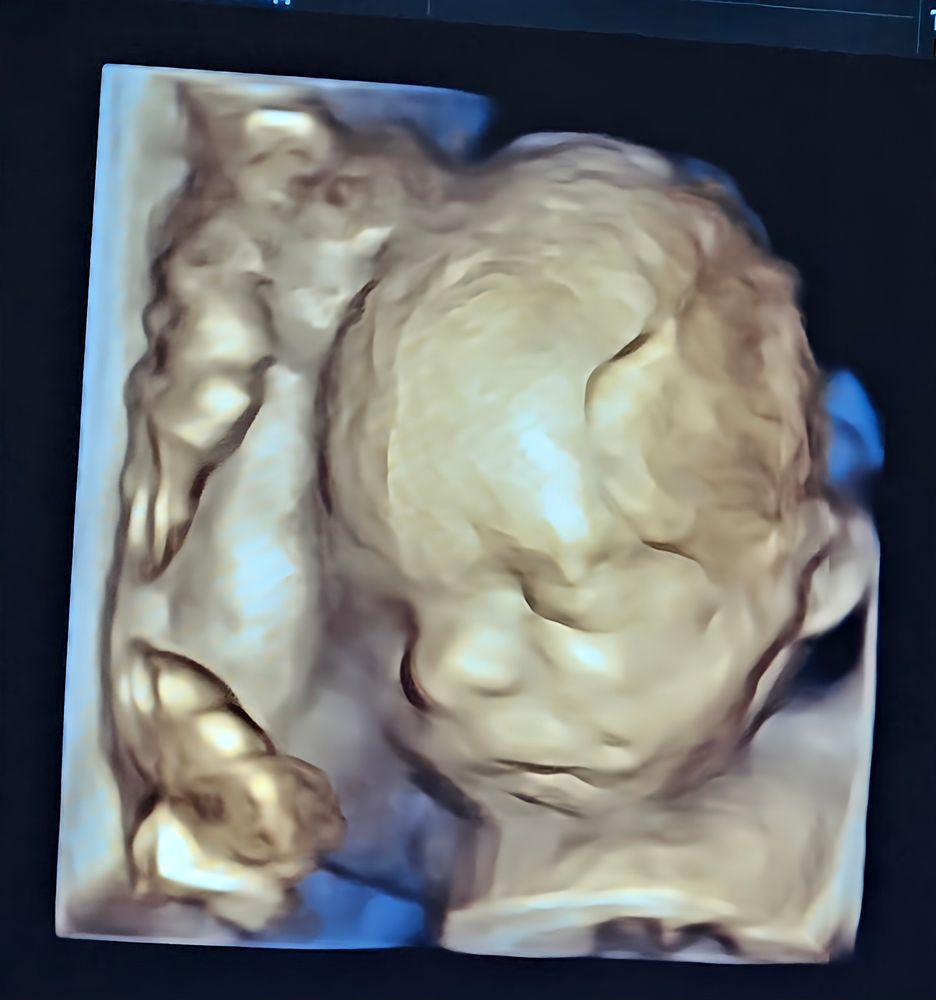

И хотела поделиться фоточкой, которую на днях мне в ЖК сделали

Вот такой вот сладкий карапуз. Спит днем. Удобненько ему, ручку под голову сложил и отдыхает 🥰